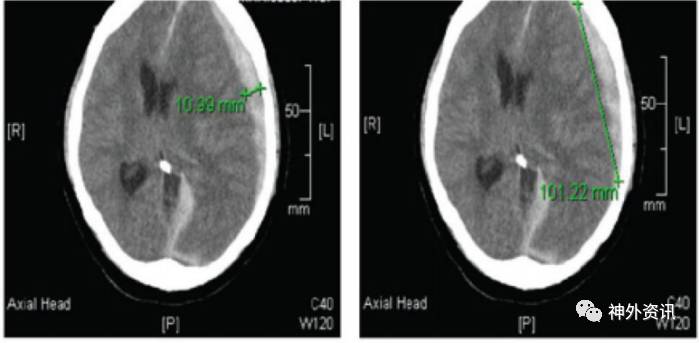

研究共纳入80例aSDH患者。作者将<65岁者归入年轻组,44例;>65岁者归为老年组,36例。从患者的年龄、性别、入院时抗凝剂和抗血小板药使用情况、手术干预或药物干预、血肿体积(图1)、凝血酶原时间、INR和临床症状等方面进行比较研究;依据入院时与1个月后血肿体积变化来评估疾病进展情况(图2)。

图1. 头颅CT扫描显示左额颞急性硬膜下血肿。新月形的血肿体积=ABC*5/2(A=宽度;B=高度;C=CT层数)。